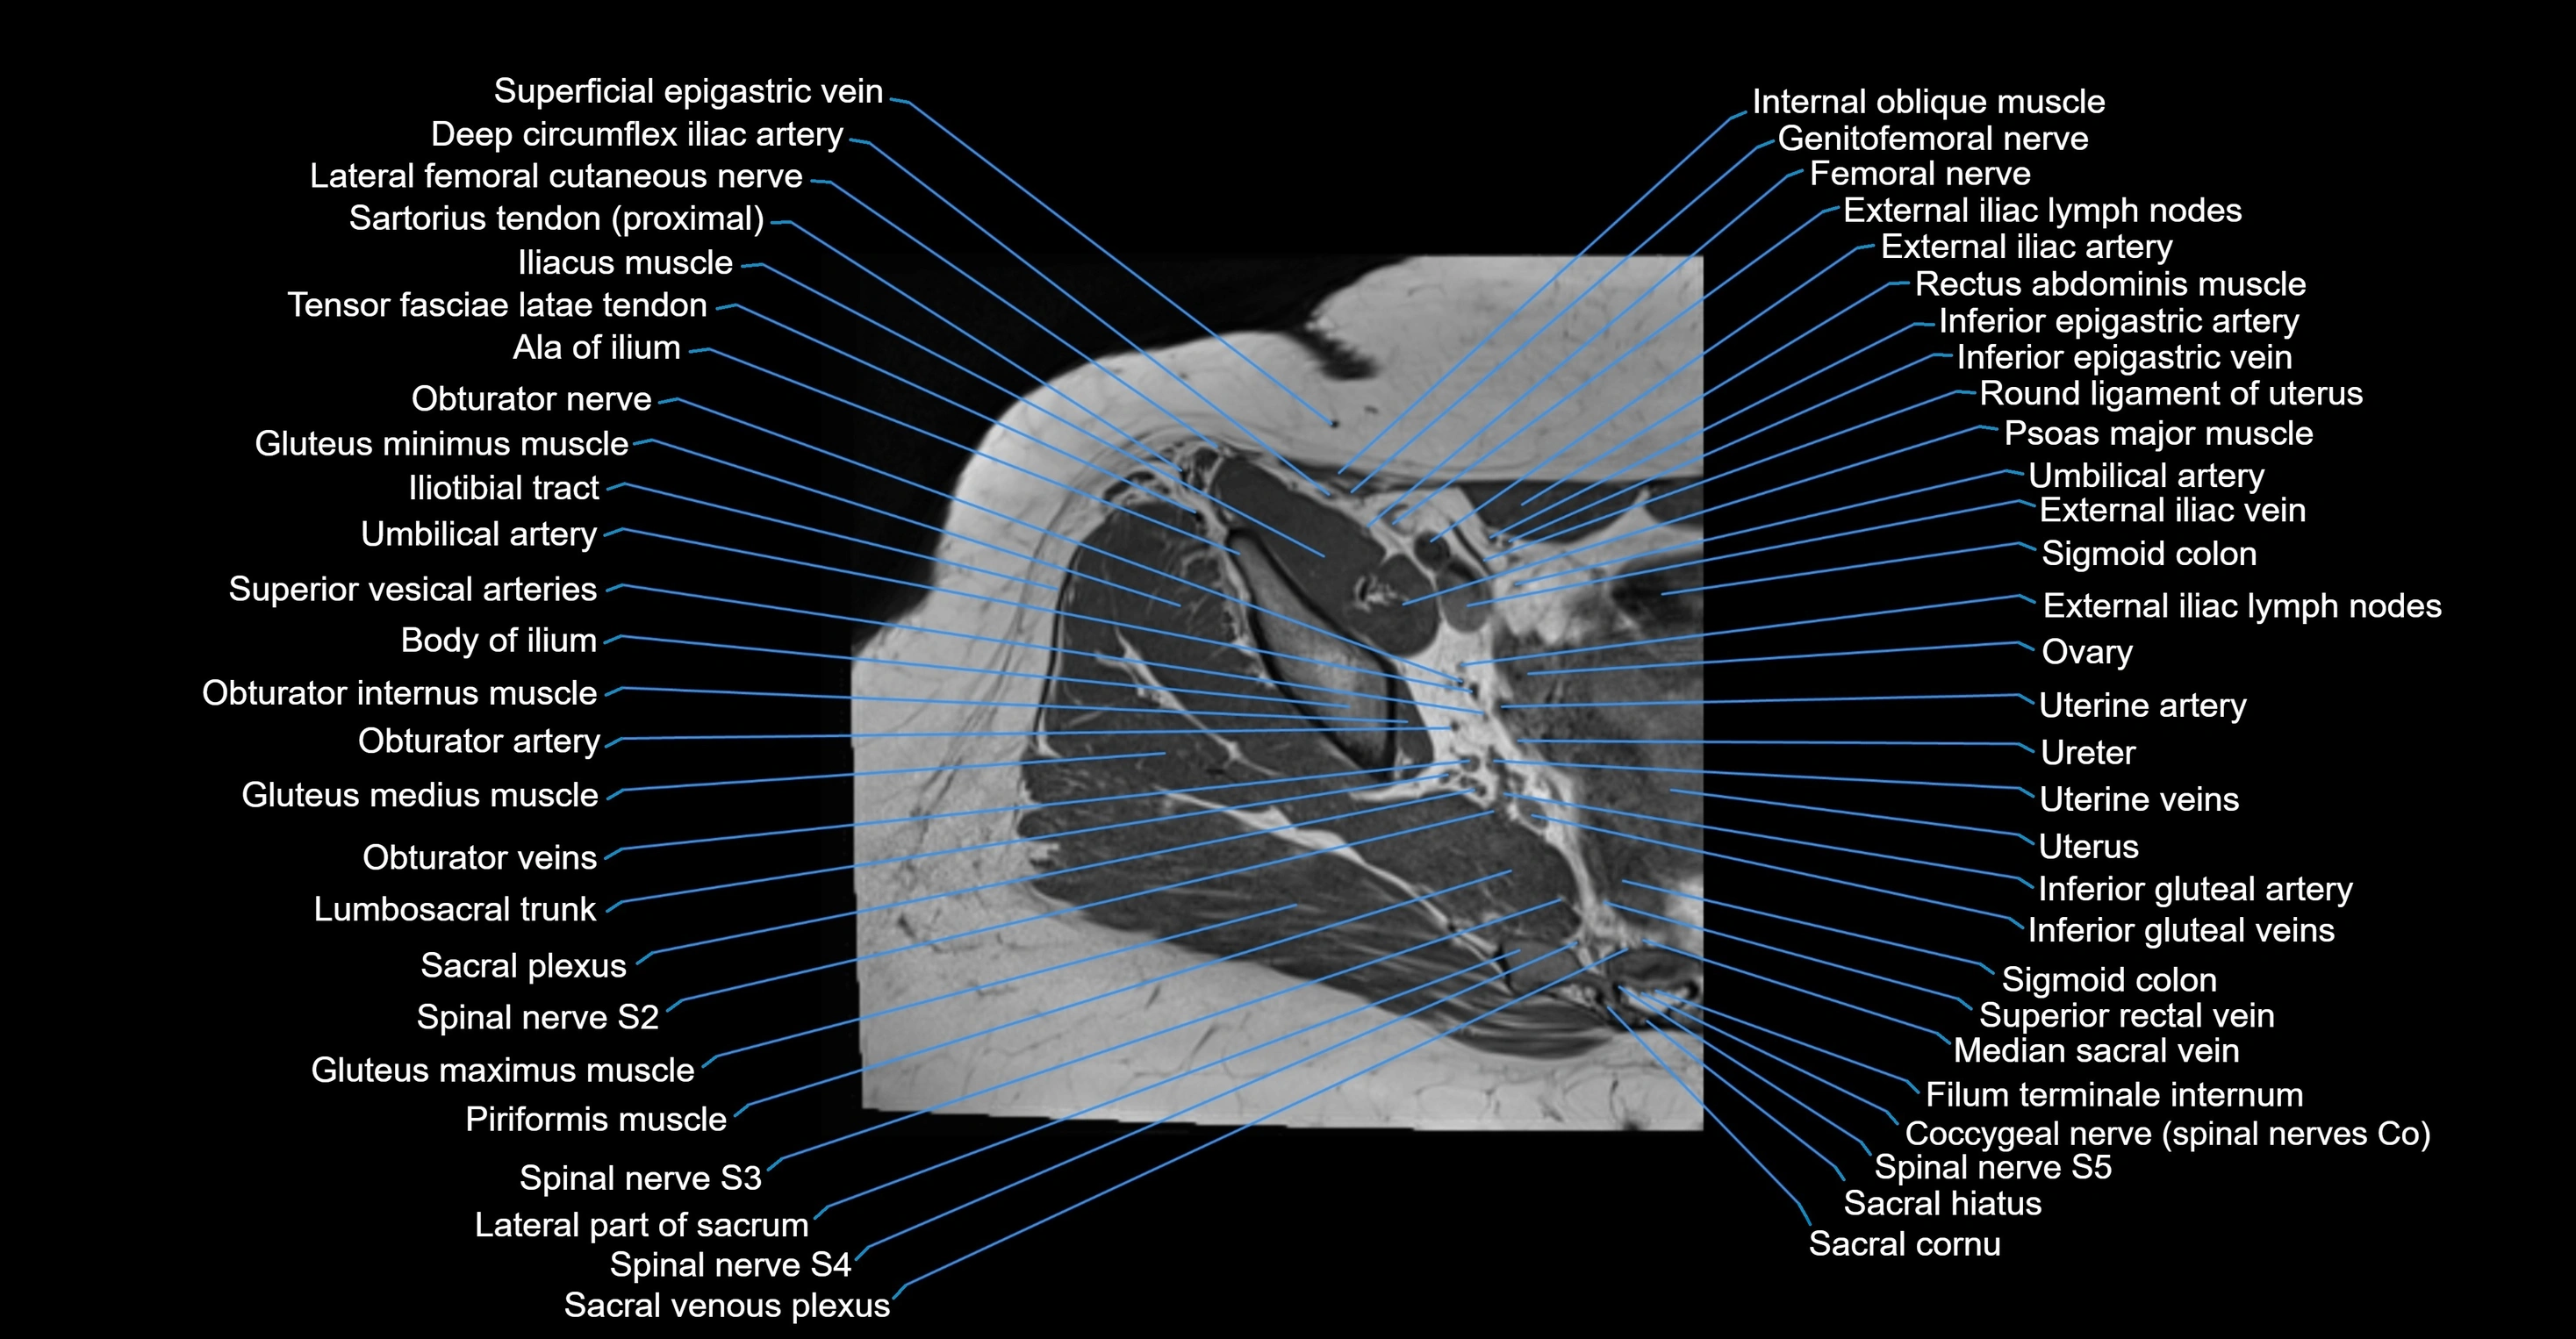

- Ala of ilium (wing of ilium)

- Ala of sacrum

- Body of ilium

- Coccygeal nerve

- Coccygeal plexus

- Coccyx

- Deep circumflex iliac artery

- External iliac artery

- External iliac lymph nodes

- External iliac vein

- Filum terminale internum

- Genitofemoral nerve

- Gluteus maximus muscle

- Gluteus medius muscle

- Gluteus minimus muscle

- Iliotibial tract

- Inferior epigastric artery

- Inferior epigastric veins

- Inferior gluteal artery

- Inferior gluteal vein

- Lateral part of sacrum

- Lumbosacral trunk

- Median sacral vein

- Obturator artery

- Obturator internus muscle

- Obturator nerve

- Obturator veins

- Ovaries

- Round ligament of uterus

- Sacral cornu (sacral horn)

- Sacral hiatus

- Sacral plexus

- Saphenous nerve

- Sigmoid colon

- Spinal nerve S2

- Spinal nerve S3

- Spinal nerve S4

- Spinal nerve S5

- Superior rectal vein

- Superior vesical artery

- Umbilical artery

- Uterine artery

- Uterine venous plexus

- Uterus